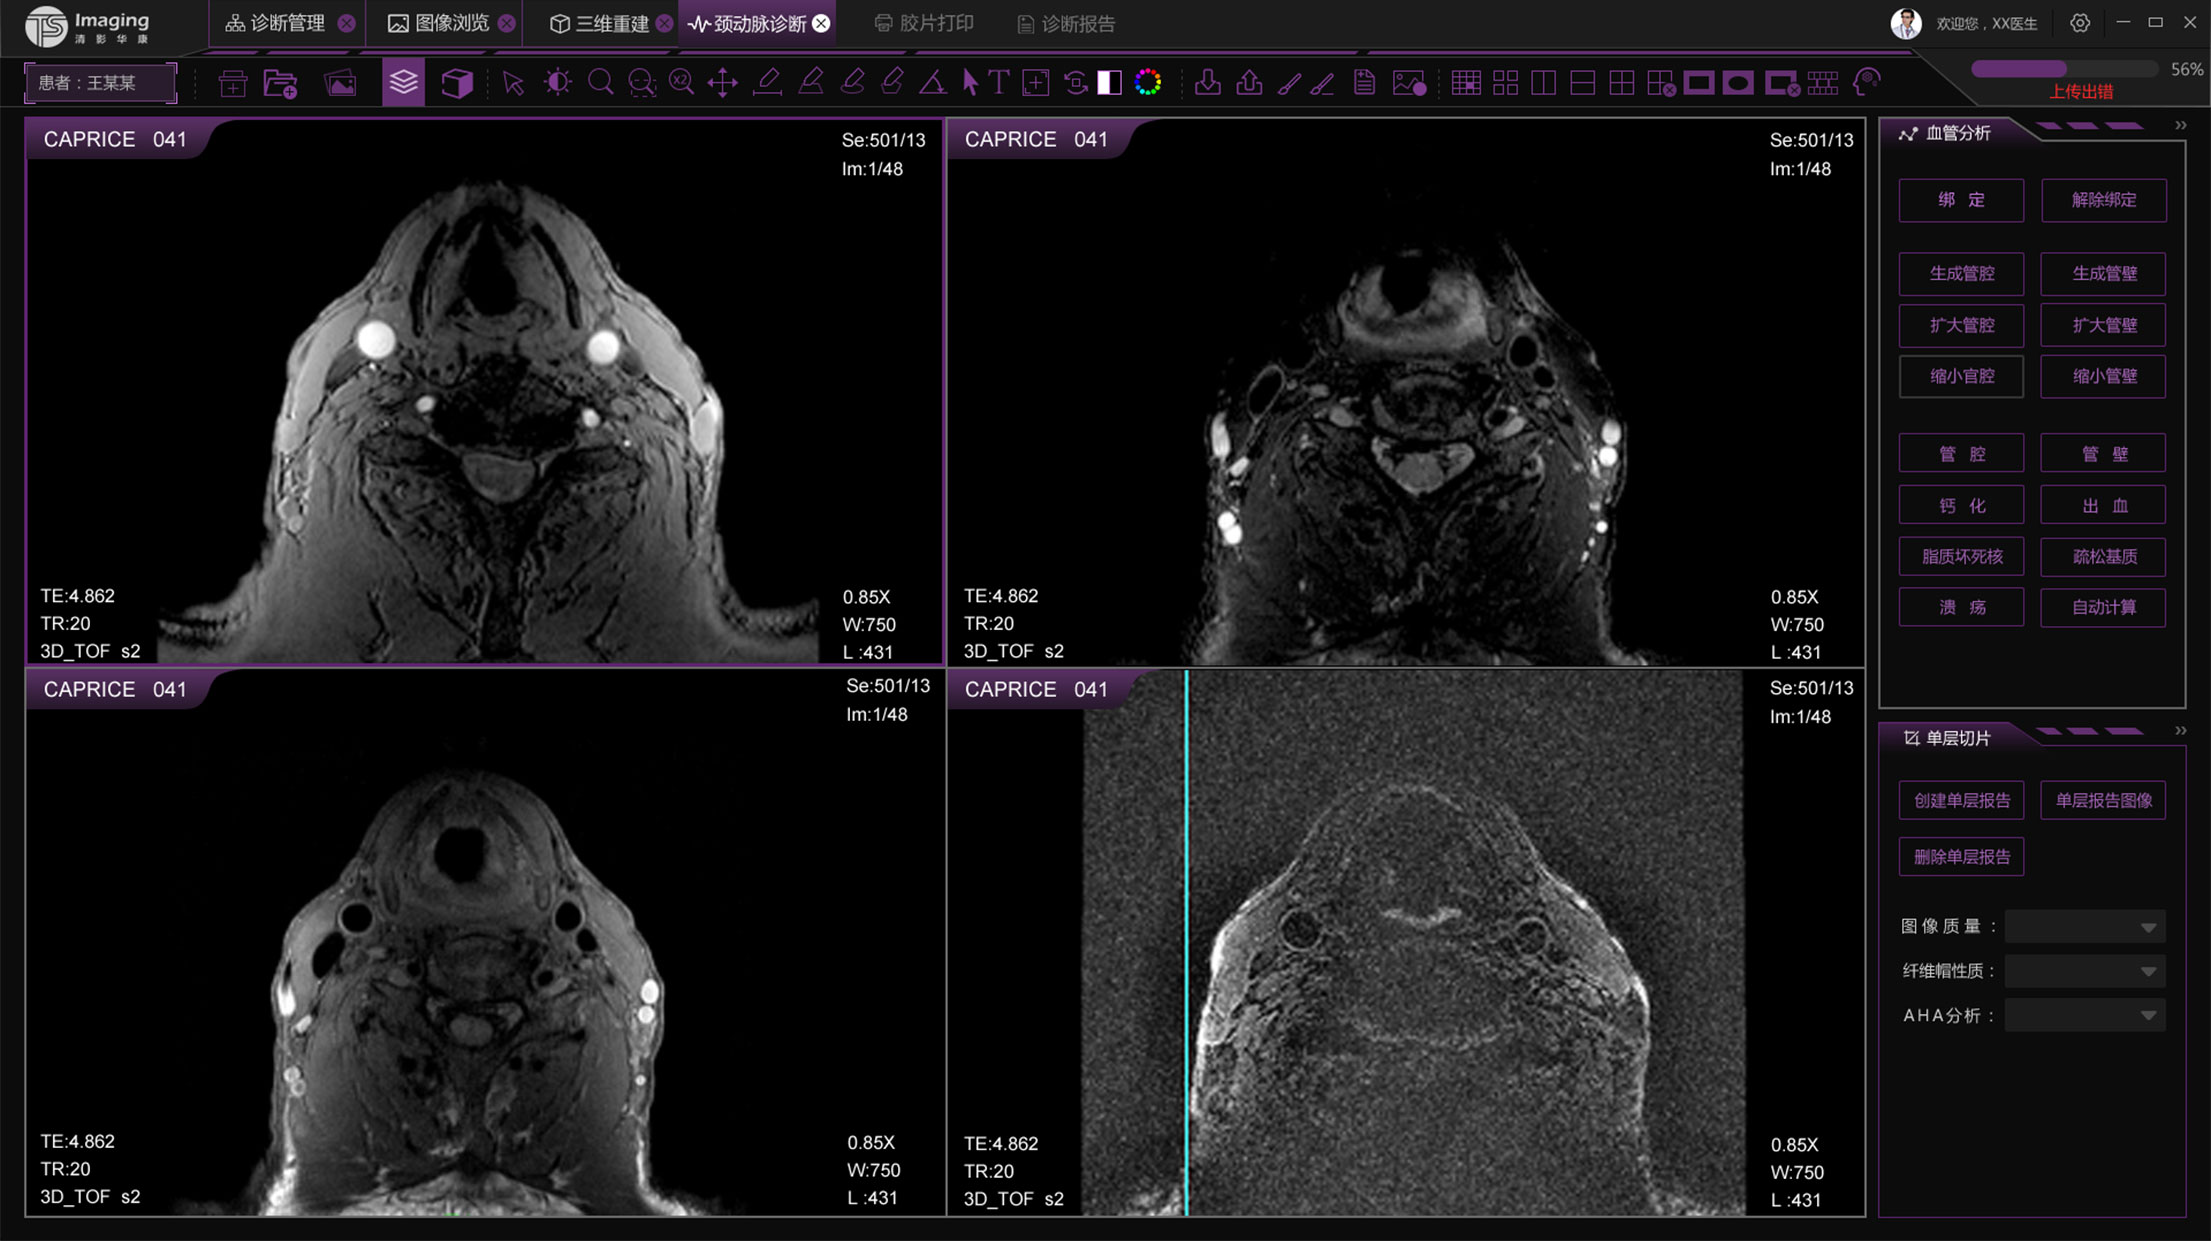

頸動(dòng)脈診斷頁面

頸動(dòng)脈診斷頁面整體布局和三維重建比較相似,最大的區(qū)別是右側(cè)的操作區(qū)域,血管分析都為按鍵操作,通過間隔的大小分成三部分。單層切片除了按鍵還有下拉菜單的操作。

這是雙方首次溝通后出的兩個(gè)方案,方案以深灰為主,考慮到該軟件是醫(yī)療圖像處理軟件,以深灰為主可以突出要操作的信息,同時(shí)上時(shí)間操作不會刺眼,緩解視覺壓力。方案二是在方案一的基礎(chǔ)上做了色彩搭配的的調(diào)整,為了使整體的色調(diào)和 公司logo的顏色更加協(xié)調(diào)統(tǒng)一。

客戶反饋這兩方案比較普通,想頁面有科技感一點(diǎn),同時(shí)也給我們提供一些他們認(rèn)為比較好的設(shè)計(jì),我們雙方再次討論后出的第三套方案,客戶也比較認(rèn)同。